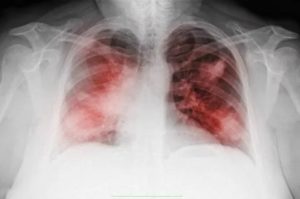

Воспаление, поражающее легочные ткани, диагностируется разными методами: клиническими, рентгенологическими, лабораторными. Одним из характерных проявлений патологии является появление дыхательных шумов, отсутствующих, если органы дыхания здоровы. Различного характера хрипы при пневмонии свидетельствуют о протекании патологического процесса.

Помимо основного дыхания, при аускультации прослушиваются и другие шумы, говорящие о том, что легкие поражены патологическим процессом. При пневмонии они бывают следующих типов:

Пневмония в большинстве случаев сопровождается именно влажными хрипами. Их возникновение обусловлено прохождением воздуха по полостям, заполненным большими объёмами мокроты.

Такие хрипы выражены, напоминают булькающий звук. Они слышны не только над очаговыми поражениями, но и при прослушивании всей полости легких как в фазе вдоха, так и при выдохе.

При пневмонии в альвеолах образуется экссудат, а также изменяются параметры сурфактанта. Из-за этого альвеолы схлопываются, а в конечной фазе вдоха резко раскрываются. Этим и обусловлен звук, напоминающий хруст или треск, называющийся крепитацией. Шумы этого типа становятся слышны примерно на вторые сутки развития воспаления и полностью исчезают после выздоровления.